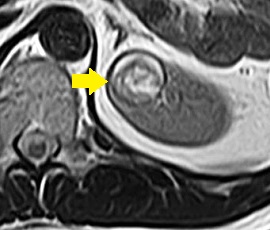

MRI画像(T2強調画像)